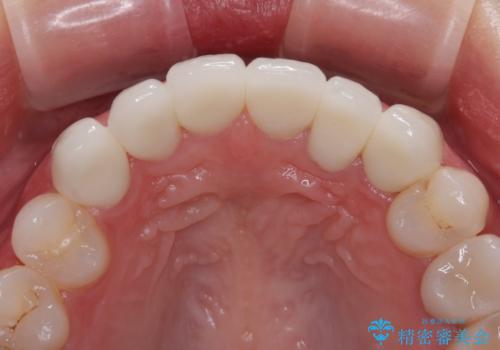

矯正治療自体はインビザラインで満足のいく仕上がりとなりました。

欠損部位は傾斜歯軸を起き上がらせることができたため、オールセラミッククブリッジにて補綴治療を行いました。

全顎的に満足のいく仕上がりとなりました。